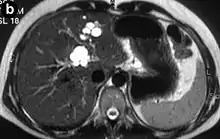

Turbo spin echo T2-weighted axial MRI of Caroli disease, showing cystic dilatations of bile ducts (shown as white).[1] | |

Modern imaging techniques allow the diagnosis to be made more easily and without invasive imaging of the biliary tree.[9] Commonly, the disease is limited to the left lobe of the liver. Images taken by CT scan, X-ray, or MRI show enlarged intrahepatic (in the liver) bile ducts due to ectasia. Using an ultrasound, tubular dilation of the bile ducts can be seen. On a CT scan, Caroli disease can be observed by noting the many fluid-filled, tubular structures extending to the liver.[4] A high-contrast CT must be used to distinguish the difference between stones and widened ducts. Bowel gas and digestive habits make it difficult to obtain a clear sonogram, so a CT scan is a good substitution. When the intrahepatic bile duct wall has protrusions, it is clearly seen as central dots or a linear streak.[10] Caroli disease is commonly diagnosed after this “central dot sign” is detected on a CT scan or ultrasound.[10] However, cholangiography is the best, and final, approach to show the enlarged bile ducts as a result of Caroli disease.